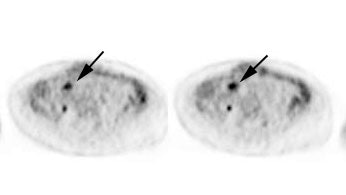

Initial staging for extrahepatic metastases: The patient below underwent FDG PET imaging to assess for extrahepatic metastatic disease prior to definitive surgical intervention. The PET exam demonstrates uptake within two hepatic metastases (black arrows on PET scan and yellow arrows on CT images) and in the patients primary colon cancer (blue arrow on PET scan and white arrow on CT image). No other sites of abnormal tracer uptake were identified which supports surgical intervention in this case. |